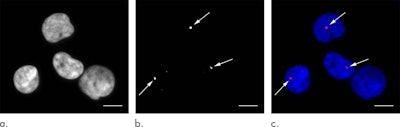

The researchers found that there was a statistically significant increase in the number of DNA double-strand breaks (p < 0.001) and chromosome aberrations (p = 0.003) in individuals after undergoing a standard CT exam, compared with before the exam. Conversely, there were no statistically significant increases in DNA damage and chromosome aberrations in the individuals who underwent a low-dose CT exam.

Increase in DNA double-strand breaks after CT | 0.05 γ-H2AX foci per cell* | 0.02 γ-H2AX foci per cell |